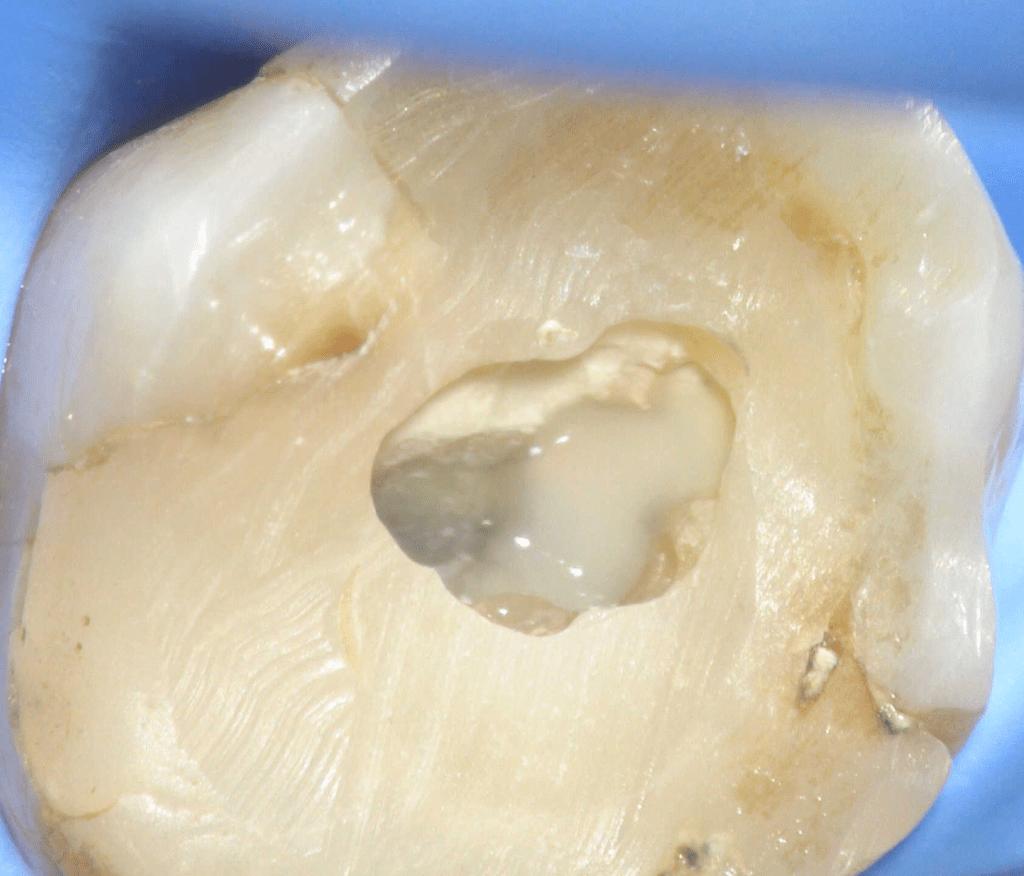

Pulpotomía biodentine + reco preendio